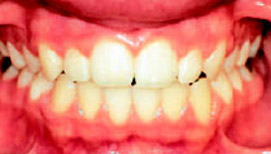

Рис.10: Пациентка с односторонним перекрестным прикусом с боковым смещением нижней челюсти, имеющая жалобы на боли в области ВНЧС.

Рис.11: Та же пациентка с металлокерамический протезом.

Рис.12а,b: После лечения: жалоб нет, правильное смыкание зубов. Результат лечения достигнут только путем коррекции положения нижних резцов и устранения смещения ни жней челюсти.